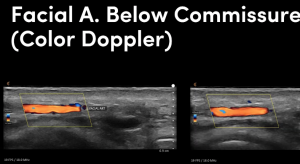

We have been working blindly for many years. And now we can confidently train you to be able to fully map out the face in terms of arteries and much more. We can measure depths of arteries and diameters and much much more.

Our course is a fully comprehensive course that not only provides you with the only ultra high frequency portable ultrasound in the world but also teaches you exactly how to use it to its best effectiveness. Over this two day course. You will cover off complications to the very highest level. Along with the most in depth anatomy training available anywhere.